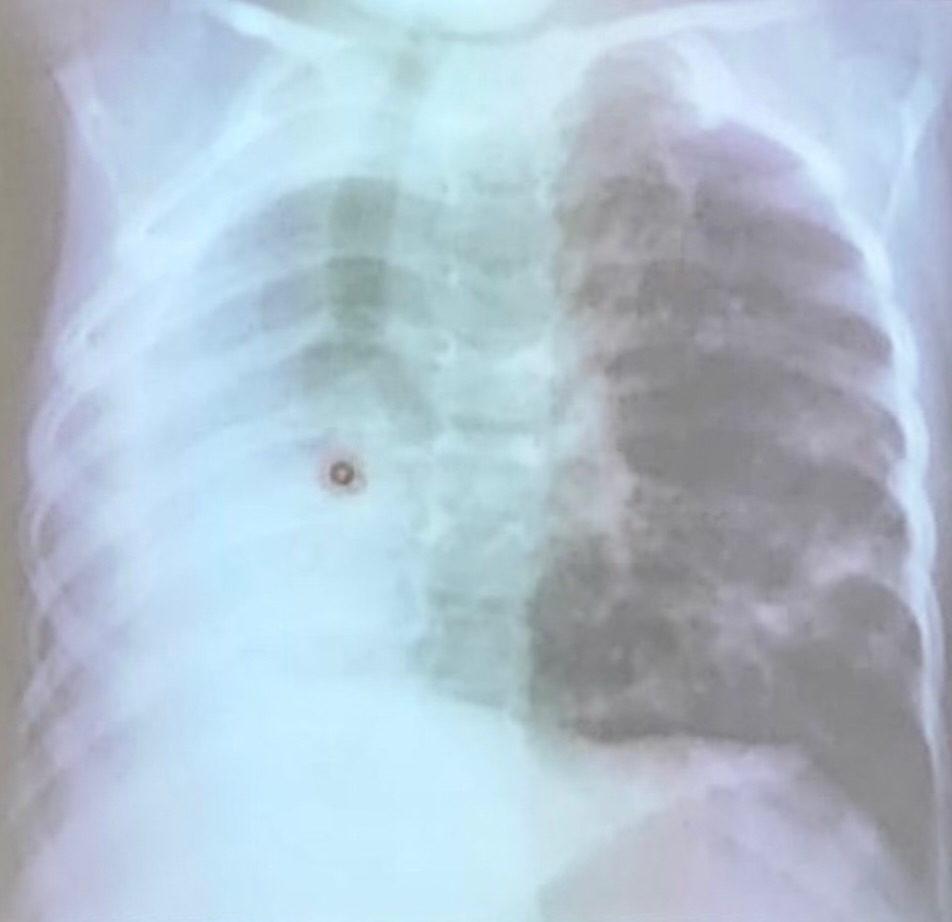

atelectasia